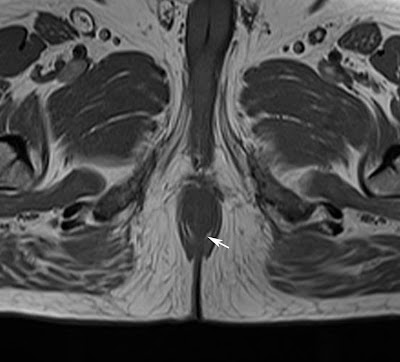

MRI - Hyperintense on both T1 and T2 weighted images due to its fat content and appears hypointense on fat suppressed T1 images.

If the fatty tissue is scanty in-phase and out-phase images T1 weighted sequence is very helpful in identifying the fat component in the lesion, which is seen as loss of signal on out-phase images.